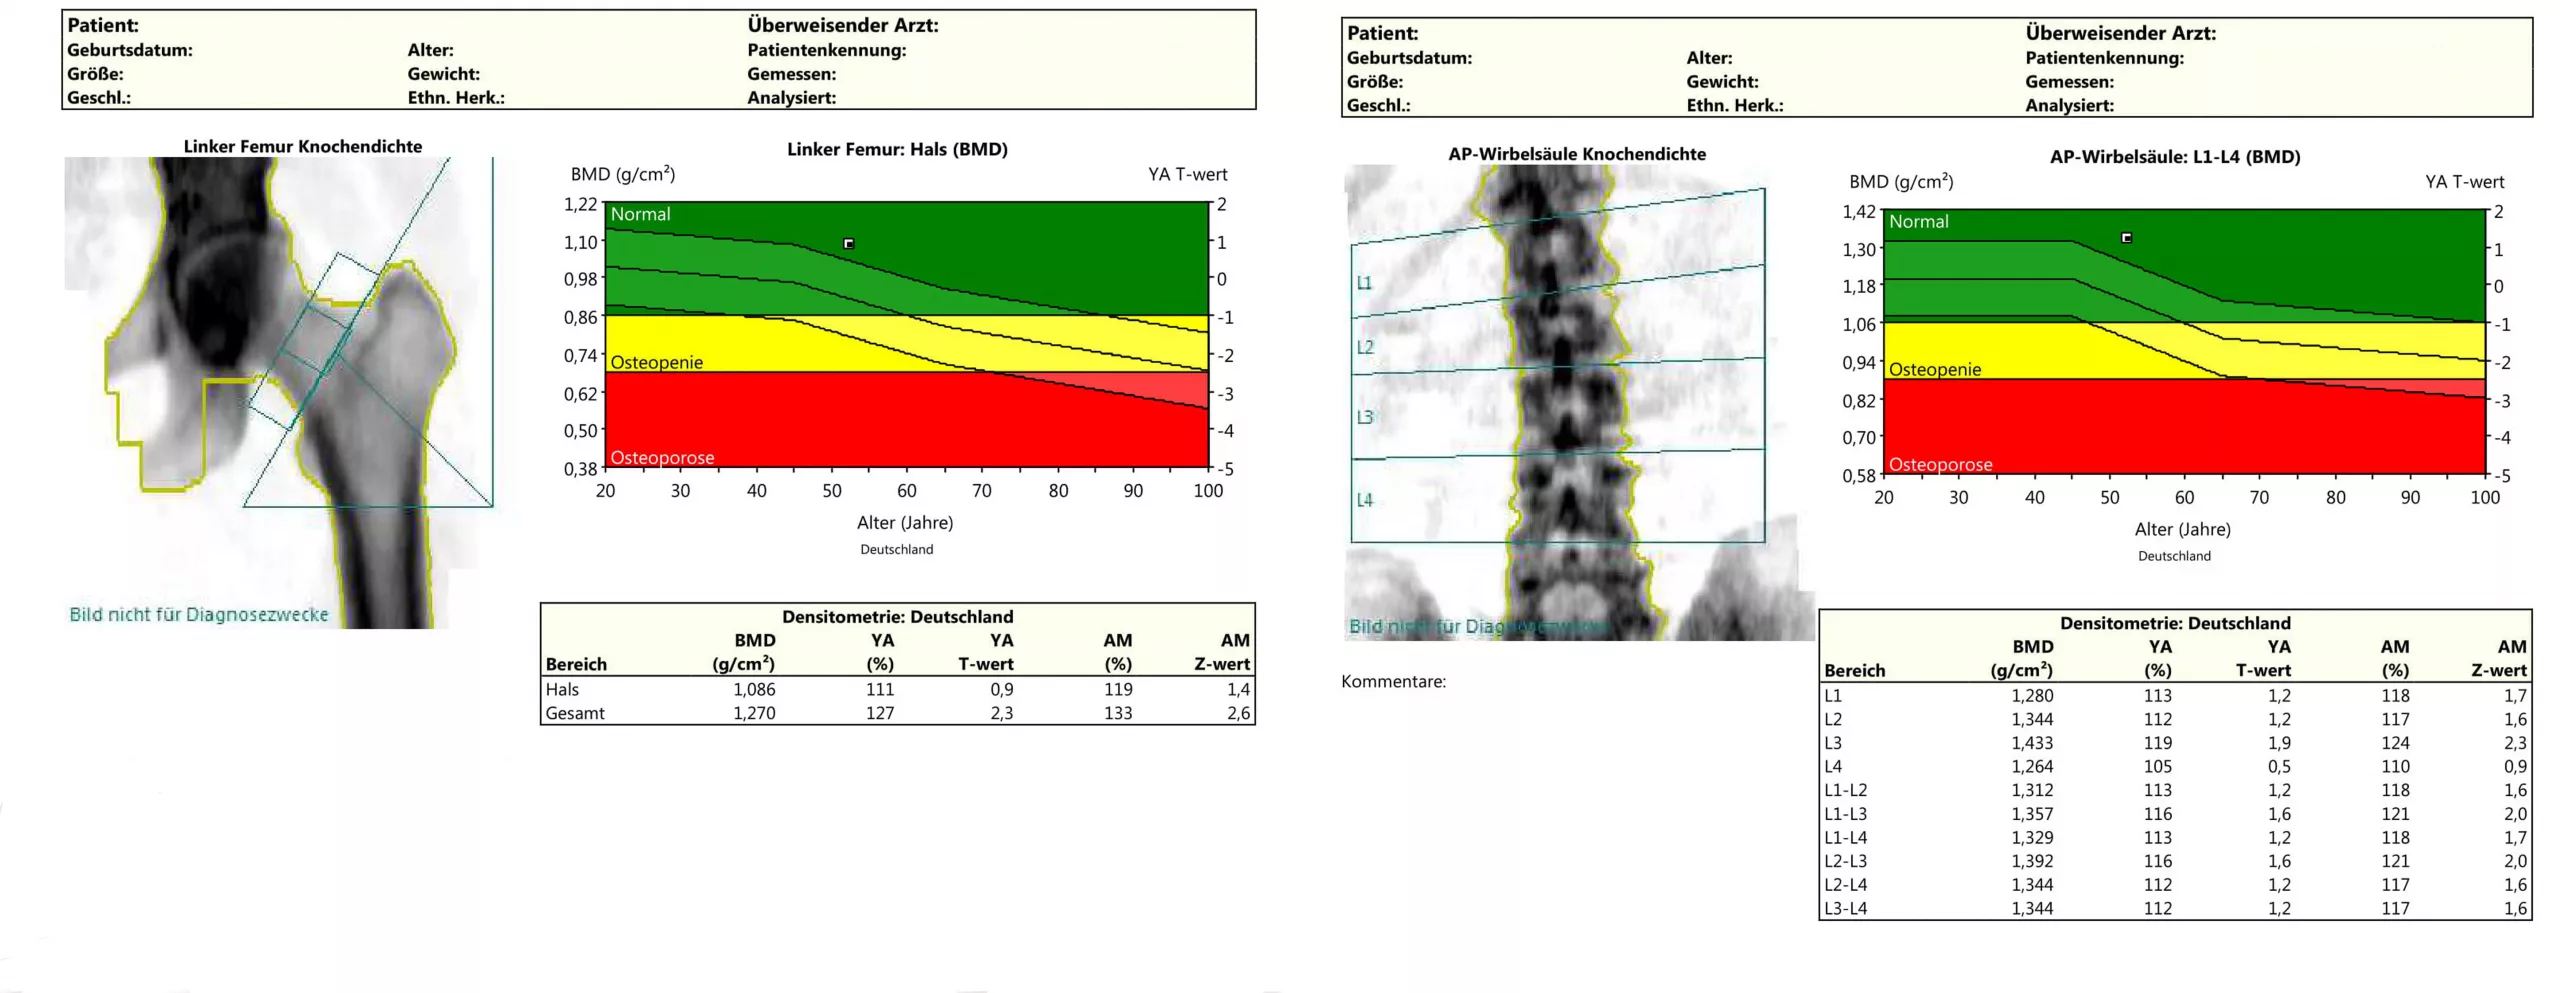

Aus den Messdaten werden dann der sogenannte T-Score und Z-Score errechnet.

Liegt der Knochendichtewert unterhalb eines T-Scores von -2,5 (-2,5 Standardabweichung vom Maximalwert bei 30-jährigen), liegt nach der Definition der WHO eine Osteoporose vor. Bei T-Werten zwischen -1,0 und -2,5 liegt eine erniedrigte Knochendichte als Hinweis auf eine Osteopenie vor. Hier empfiehlt sich eine Verlaufskontrolle nach einigen Jahren.

Der Z-Wert ist ein Wert, der sich auf gesunde Männer bzw. Frauen gleichen Alters bezieht.